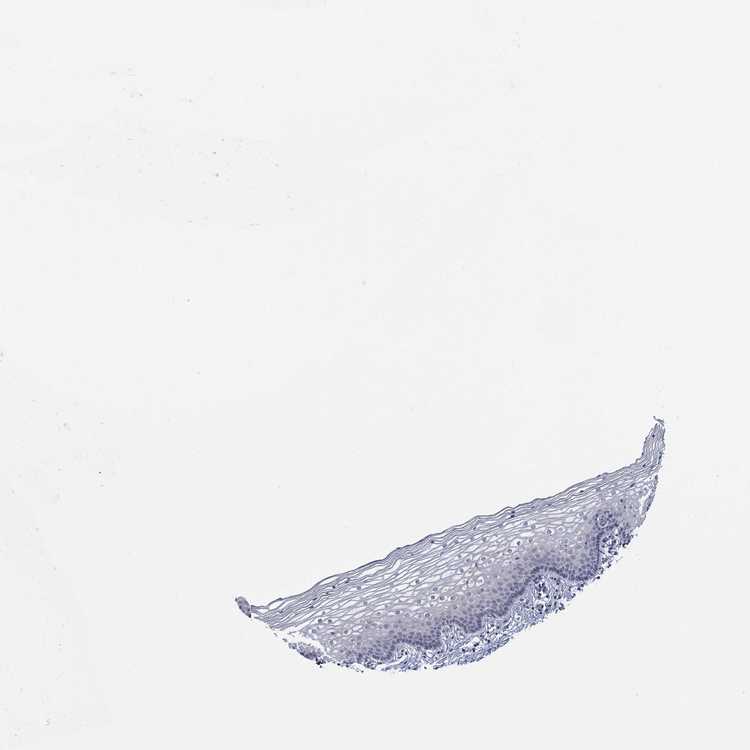

TISSUE PRIMARY DATA VAGINA Show tissue menu

Vagina

VAGINA - Antibody stainingi

Antibody staining in the annotated cell types in the current human tissue is reported as not detected, low, medium, or high, based on conventional immunohistochemistry profiling in selected tissues. This score is based on the combination of the staining intensity and fraction of stained cells.

Each image is clickable and will lead to virtual microscopy that enables deeper exploration of all samples and also displays staining intensity scores, fraction scores and subcellular localization as well as patient and tissue information for each sample.

Antibody HPA048531Antibody HPA066469

Squamous epithelial cells Not detectedNot detected